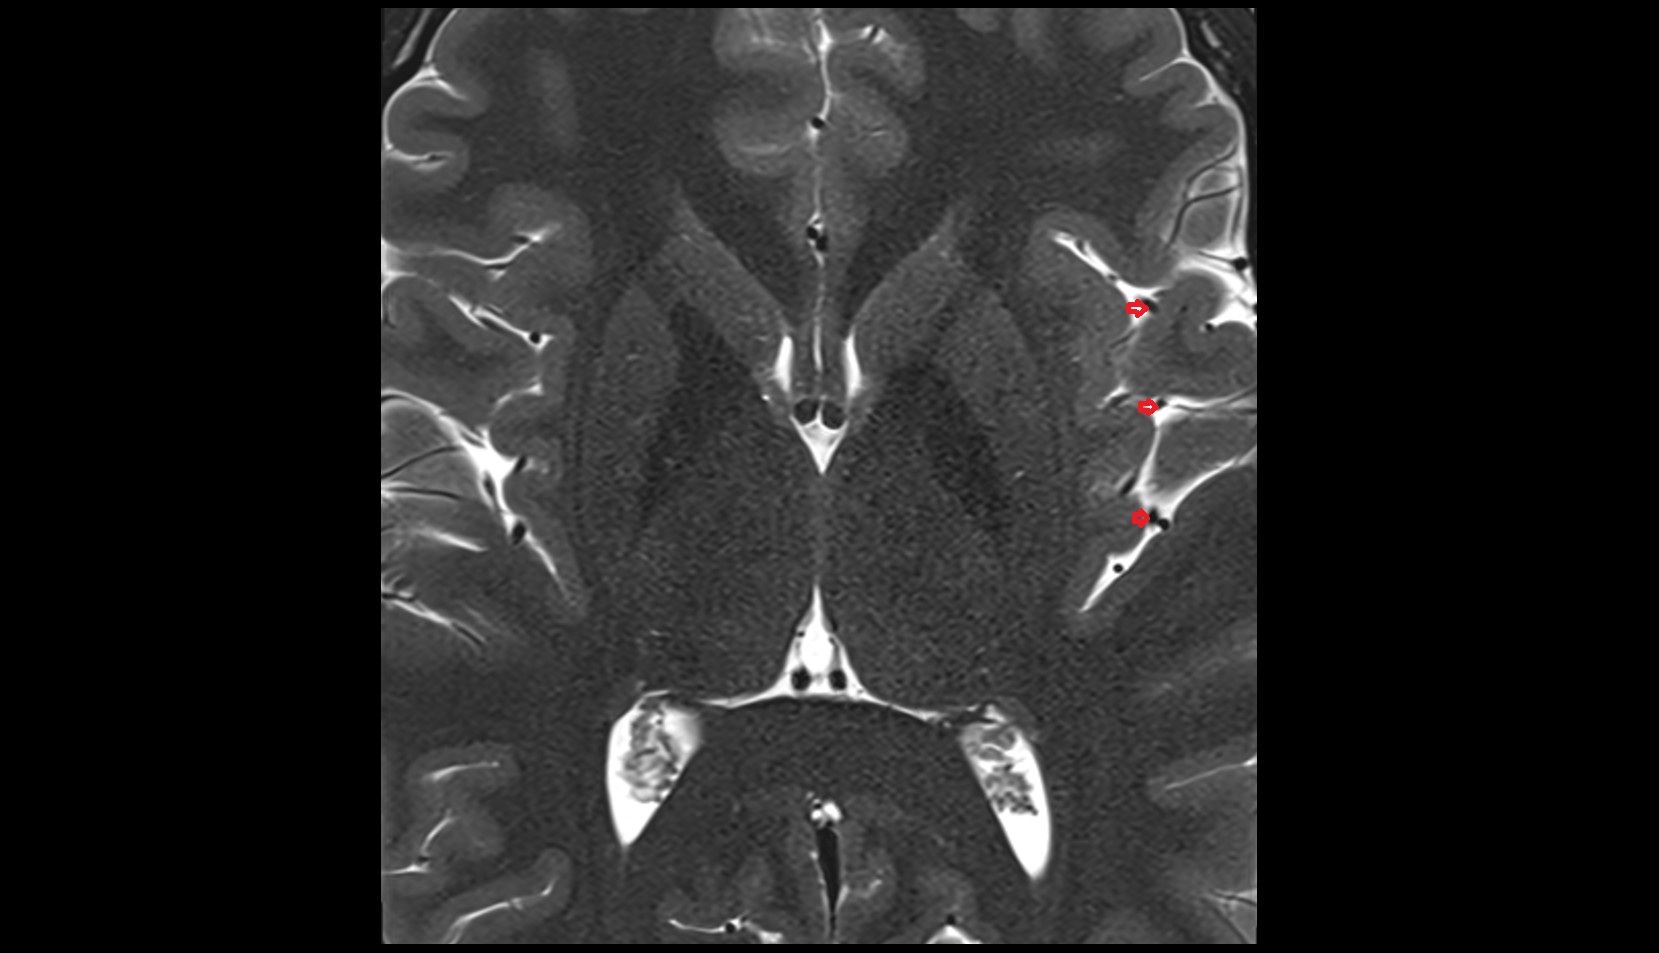

- Hippocampus

- Body of hippocampus

- Head of hippocampus

- Tail of hippocampus

- Hippocampal body

- Hippocampal head

- Hippocampal tail